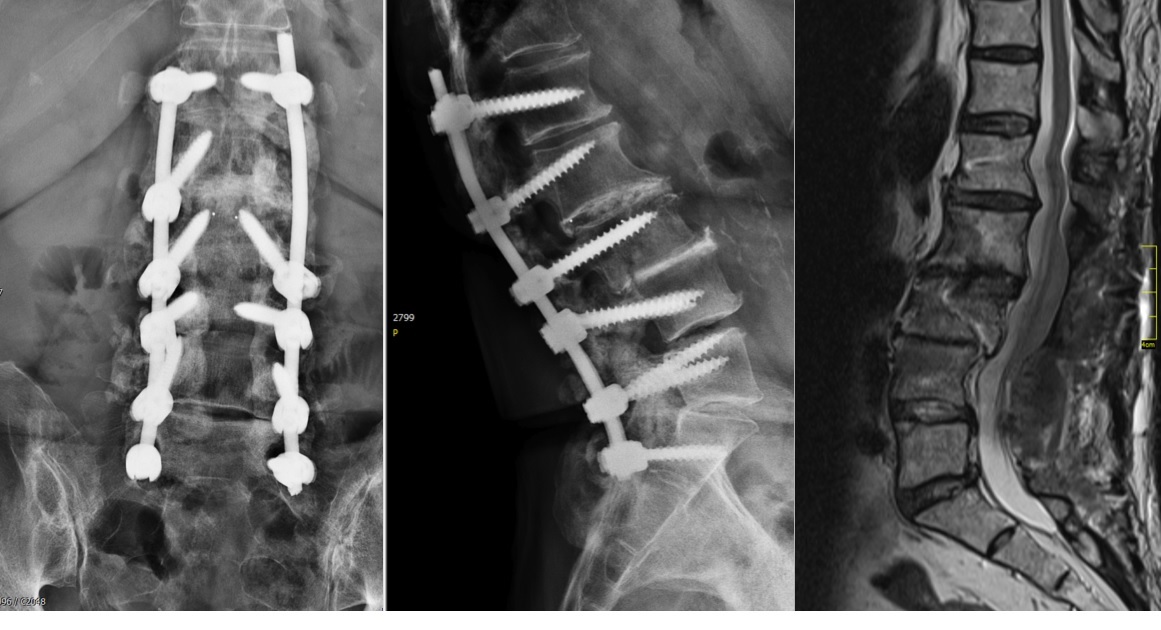

A 75-year-old female patient presented with postoperative back pain. She had been initially operated on eight years earlier with a laminectomy and fusion from L2 to L4. This proved to be successful for a number of years until a second operation was required for secondary back pain and left side leg pain. An extension of the decompression was performed with stabilization and fusion from L1 to S1. The rationale for this operation was unknown and the surgery failed to improve her symptoms.

The problem to be addressed was the patients back pain and left side leg pain, inclusive of some weakness in her left foot. The pain was present upon weight-bearing, with a pain scale of 9. Her discomfort remained at night. The patient was of slim build and was in good general health. She presented with a limp from her left hip and the dorsiflexion of the left foot was weak (M4).

The preoperative standing image of the lumbar spine revealed a flat back with no obvious degeneration of the adjacent segment L1/L2 (Fig 6ab). The implants seemed regularly placed. After wide laminectomy, the spinal canal was open over the whole lumbar spine, illustrated on the MRI scan (Fig 6c).

A CT scan allowed a more detailed assessment (Fig 7). There was an obvious nonunion at L5/S1, with loose screws in the sacrum (red circle). Furthermore, there was instability at L4/L5 as the intervertebral disc presented with an important vacuum phenomenon (asterisk). Foraminal stenosis at L5/S1 (not shown) seemed to be the reason behind the persistent leg pain.